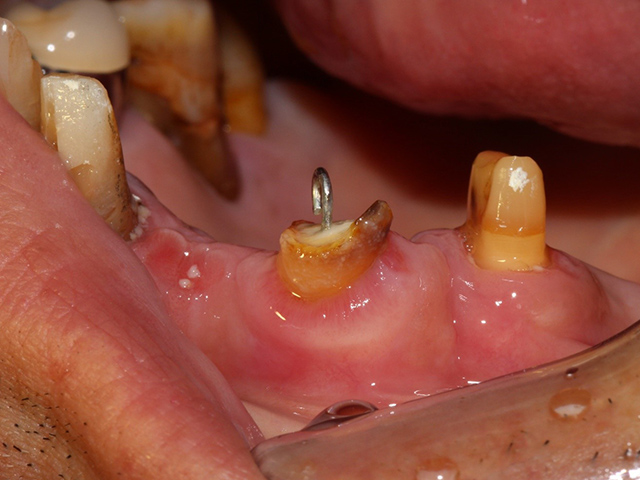

- 根っこの治療を行い、土台部分に針金でフックをかけます。

この上に仕掛け付きの仮歯を装着してゴムの力で引っ張ります。

エクストルージョンとは、歯を垂直に引っ張る部分矯正のことで、主に歯の頭部分が破折し、根っこだけ残ってしまった歯に用います。

矯正の弱い力で引っ張ることで周囲組織のダメージを最小限にし、歯周組織だけでなく、歯槽骨も同時に誘導することで、短くなってしまった根っこを最大限活用する方法です。

引っ張り上げた際についてきた歯周靭帯を切除して、歯質を高さ・厚み共に2ミリ以上確保することが出来ました。

引っ張り上げる期間は1ヶ月〜3ヶ月ほど、固定期間も1ヶ月〜3ヶ月ほどになります。

引っ張り上げた歯に土台を立てて、被せ物を行いました。

根っこだけになり残すのが難しい歯でしたが、無事に歯を残すことができました。

現在治療後6年経過していますが、問題なく機能しています。